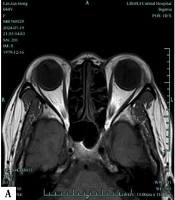

Diagnostic Accuracy of MRI-Based Dixon and T2 Localization Techniques for Imaging Severity and Progression in Thyroid-Associated Ocular Diseases